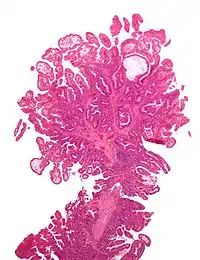

![]() На мікрофотознімку зображений поліп товстої кишки при синдромі Пейтца-Єгерса. Фарбування гематоксилін-еозин. На мікрофотознімку зображений поліп товстої кишки при синдромі Пейтца-Єгерса. Фарбування гематоксилін-еозин. | |

Діагностують синдром за допомогою біопсії. Гістологічно можна виявити у поліпах розгалужені гладком'язові клітини з закладеними залозистою тканиною.